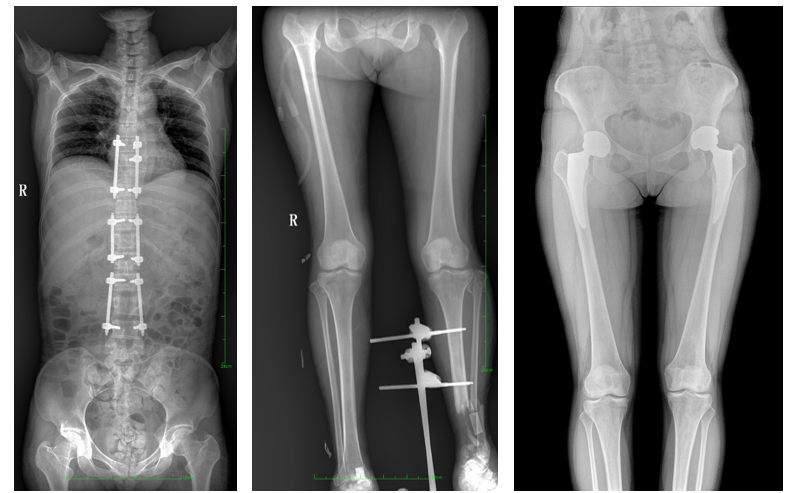

普愛醫(yī)療自主研發(fā),專為大視野臨床應用打造的平板動態(tài)DR——PLX8600,圖像不拼接,有效簡化影像科室檢查流程,提高診斷精度,降低患者吸收的輻射劑量。與市面常規(guī)多張攝影再軟件拼接DR相比,PLX8600解決了拼接圖像存在密度不均勻,拼接處圖像配準和放大效應等問題,輻射劑量是常規(guī)長骨軟件拼接DR的1/2或1/3,給患者更多關愛。

一、成像面積大。17"*34"有效視野,一次成像不拼接。相較于多張攝影再軟件拼接的DR設備,PLX8600解決了拼接圖像存在密度不均勻,拼接處圖像配準和放大效應等問題,給臨床帶來了大視野影像解決方案,可一次性覆蓋全脊柱或雙下肢影像。

PLX8600大視野平板動態(tài)DR攝影速度快,患者可以更快地完成檢查,且單次攝影輻射劑量是常規(guī)多張攝影再軟件拼接DR的1/2或1/3,低劑量給患者更多關愛。

PLX8600大視野平板動態(tài)DR可在低輻射劑量下獲得患者站立位、臥位的高質量影像。搭載自主研發(fā)的圖像均衡處理系統(tǒng),能夠很好的均衡人體不同厚度組織的影像,視野大,圖像清晰,層次豐富。如果您想采購這款產品,歡迎聯(lián)系我們,咨詢電話400-025-6366。